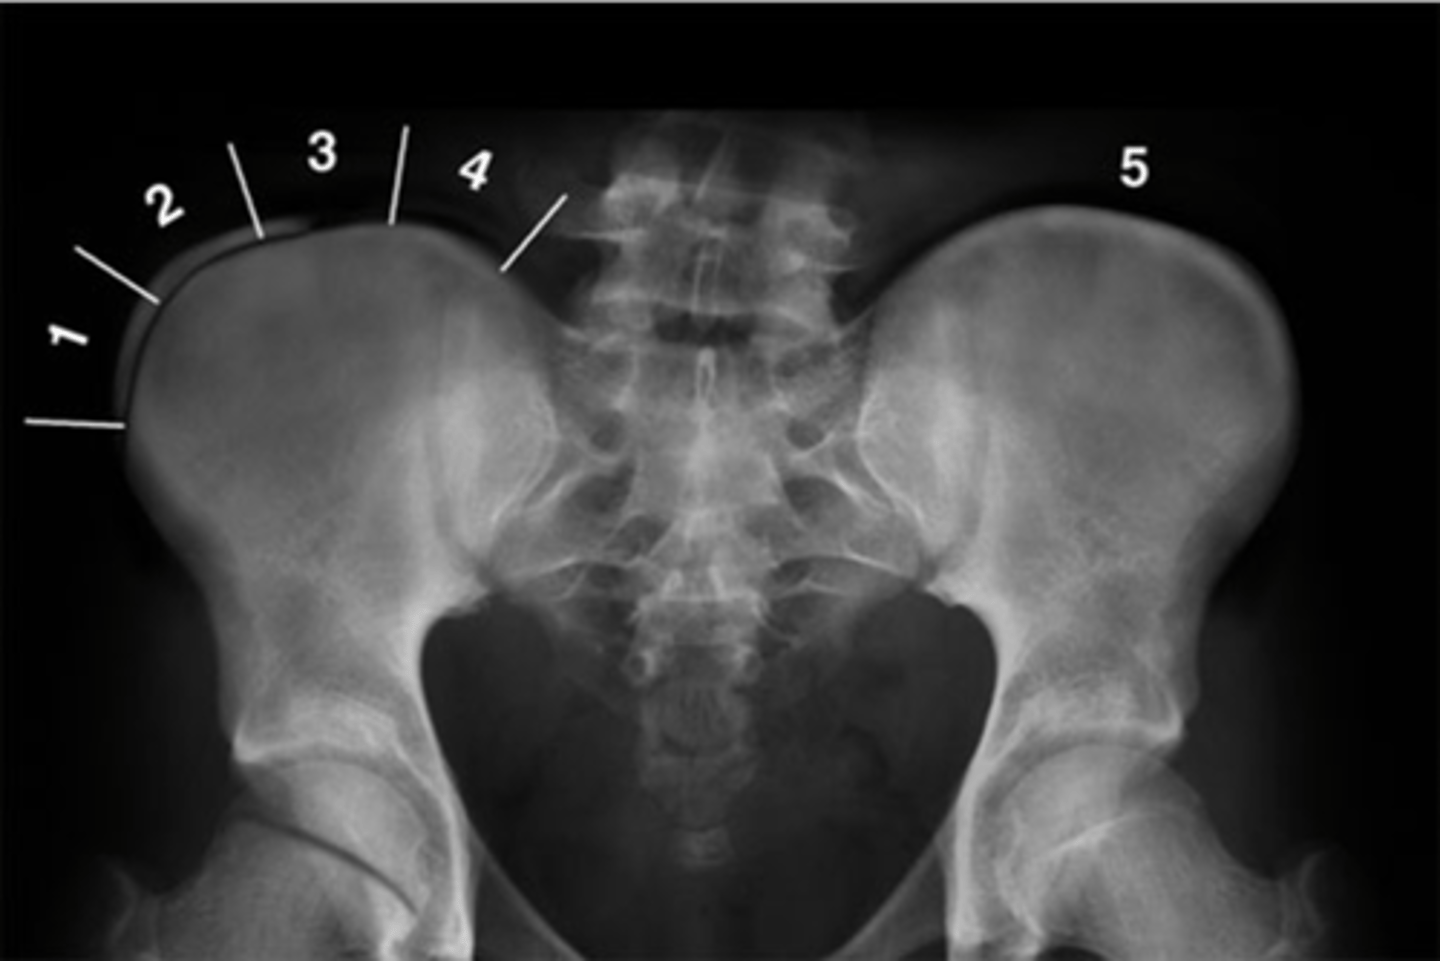

Pubic symphysis

ID 1

<p>ID 1</p>

Left femoroacetabular joint

ID 2 (joint)

<p>ID 2 (joint)</p>

Left posterior sacroiliac joint

ID 3 (joint)

<p>ID 3 (joint)</p>

Left anterior sacroiliac joint

ID 4 (joint)

<p>ID 4 (joint)</p>

9

New cards

Right: gluteus medius

Left: gluteal fat stripe

ID 5

<p>ID 5</p>